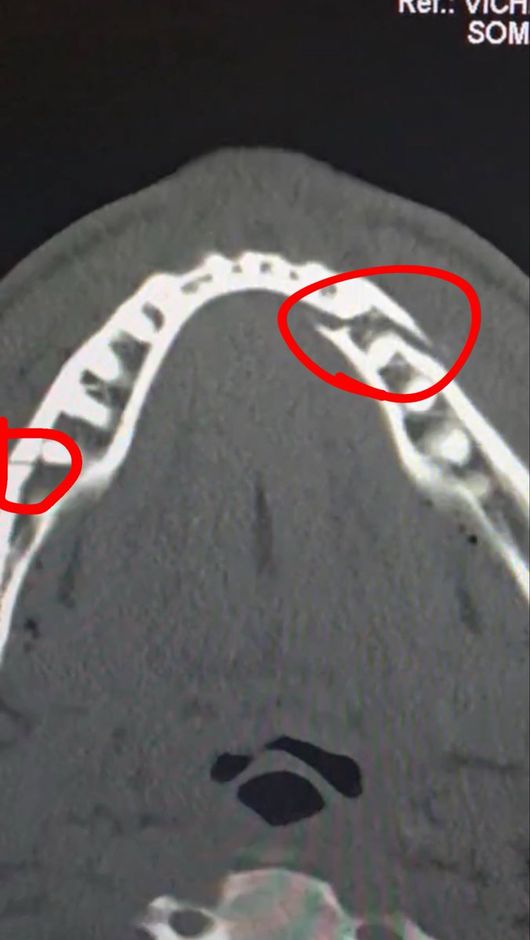

실제로 폴의 부상은 결코 가볍지 않았다. 진단 결과 그의 턱뼈는 두 곳이나 골절돼 세 동강이 난 모습이었다. 그는 곧바로 수술대에 올랐고, 티타늄 플레이트 두 개를 삽입했다. 치아도 일부 제거해 한동안 정상적인 식사도 불가능한 것으로 알려졌다.

폴은 소셜 미디어를 통해 자신의 수술 후 상태를 공개하면서 "통증이 심하지만 난 괜찮다. 턱뼈가 두 군데나 으스러졌다. 7일 동안 유동식을 먹어야 한다"라고 밝혔다. 경기를 앞두고 조슈아에게 "널 죽여버리겠다"라고 도발했던 폴이지만, 조슈아의 벽은 너무나 높았다.